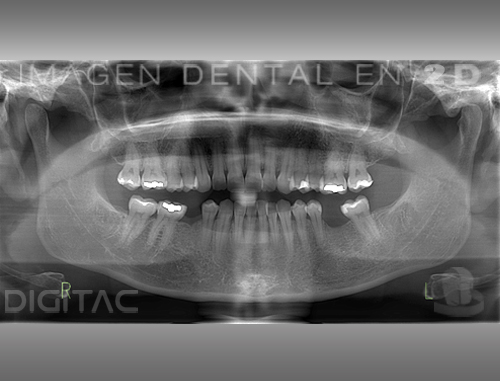

La ortopantomografía o radiografía panorámica es una técnica radiológica extraoral que ofrece una imagen completa de la zona maxilar, mandíbular y dental. Por tanto, es de gran utilidad en el área dentomaxilomandibular.

Hoy en día, la ortopantomografía es una herramienta imprescindible en todas las áreas de la odontología tanto para el diagnóstico de patologías, como para la planificación de tratamientos. El valor diagnóstico de la ortopantomografía en cirugía bucal, implantología, ortodoncia, periodoncia y en patología oral y dental es fundamental.